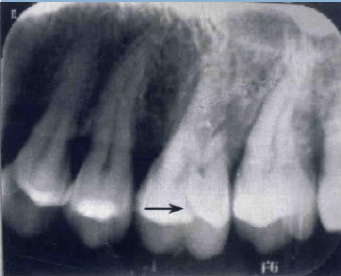

3. 對于一些難以確診的病例,還可能需要借助 X 光片、CT 等影像學(xué)檢查手段。